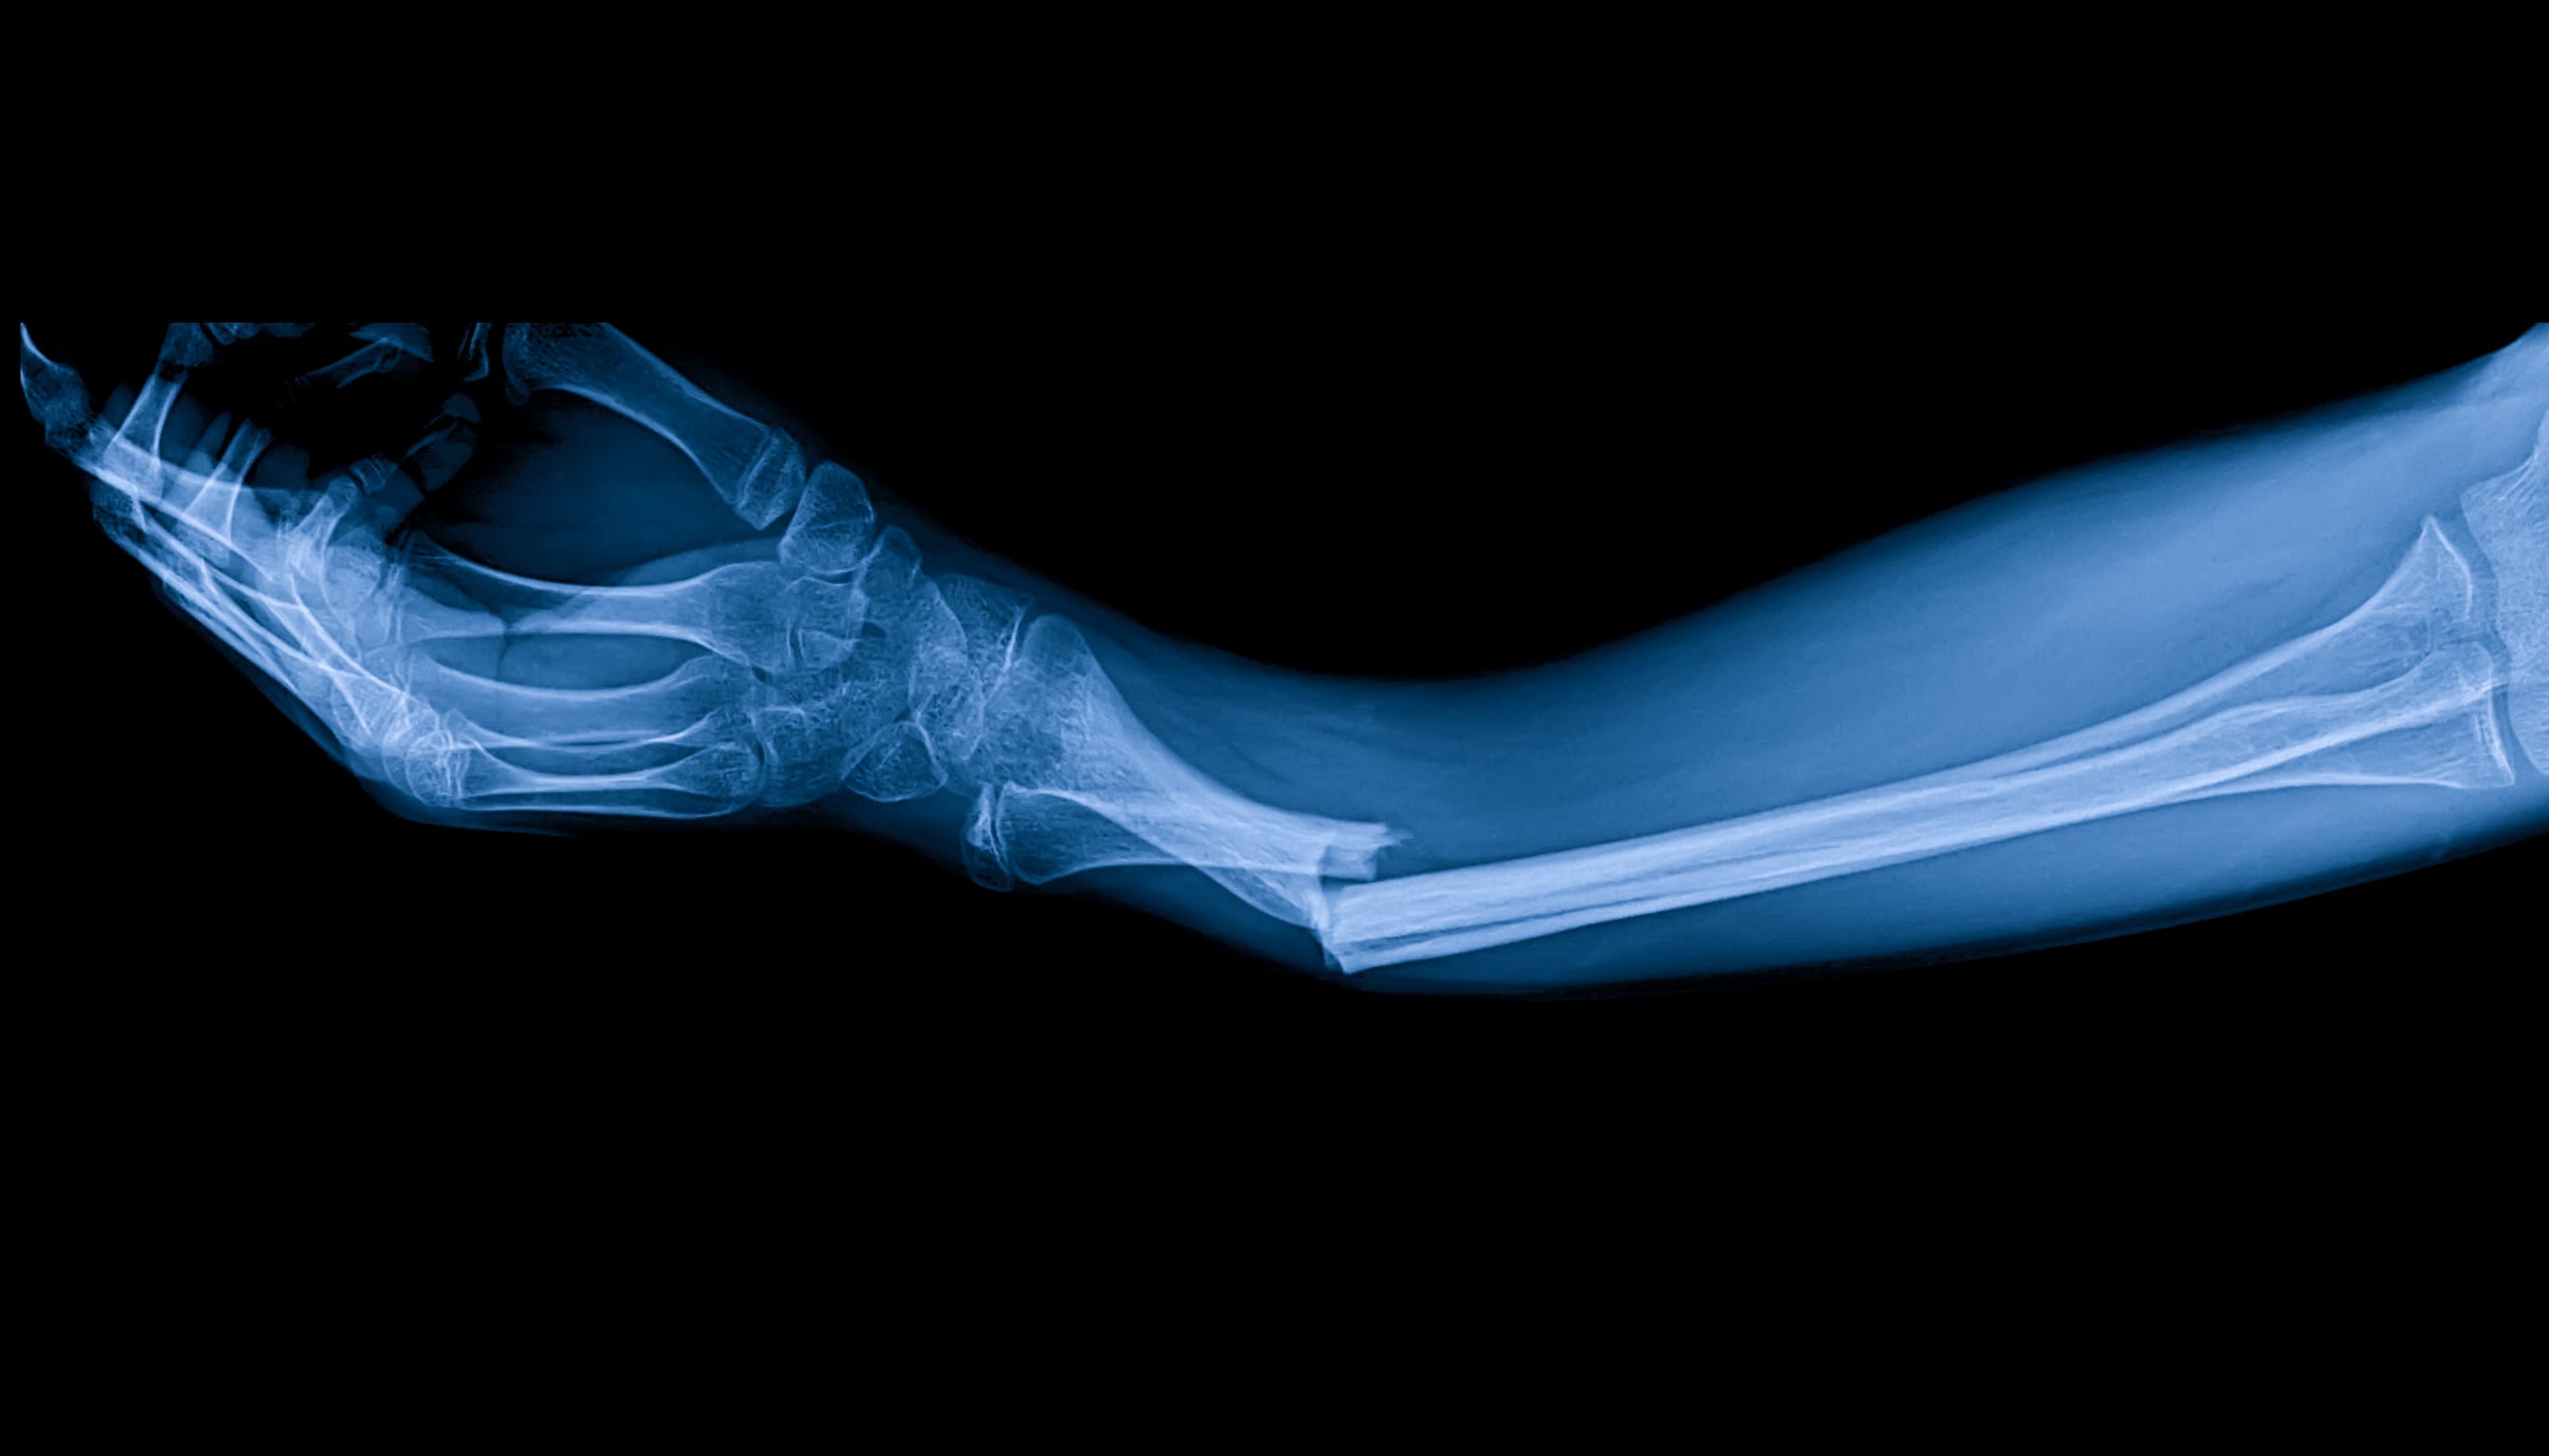

FRACTURAS ÓSEAS

Terapia PEMF para fracturas óseasLa terapia PEMF se ha investigado por su potencial para acelerar la cicatrización ósea y mejorar la recuperación de fracturas al aumentar la actividad de las células óseas y la circulación alrededor del lugar de la lesión.